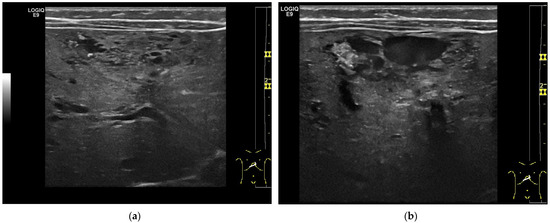

Figure 3.

Hemangioendothelioma in a 1-month-old infant. A cystic mass with a maximum diameter of 4 cm in liver segment IV with blurred borders and calcifications with dorsal acoustic shadow (a–e). Evidence of increased vascularization on color Doppler (f). Feeder artery with inflow from the hepatic artery and venous outflow via the markedly dilated left hepatic vein (g). Increased flow velocities in the coeliac trunk and hepatic artery (h,i). Outflowing left hepatic vein with arterialized flow profile and increased flow velocities (j).